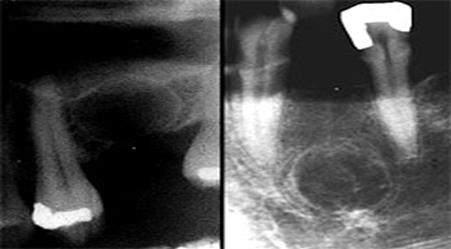

В случае удаления причинного зуба без удаления оболочки кисты формируется резидуальная киста.

Рентгенологически эта киста выглядит как четко отграниченное округлое просветление костной ткани, локализующееся в непосредственной близости к лунке удаленного зуба.

Кератокиста распространяется по длиннику челюсти и не приводит к выраженной деформации кости. Поэтому определяют ее при достижении больших размеров. Киста распространяется на тело, угол и ветвь челюсти. Рентгенологическая картина характеризуется наличием обширного разрежения костной ткани с четкими полициклическими контурами, при этом неравномерное рассасывание кости создает впечатление многокамерности. Нередко в процесс вовлекаются венечный и мыщелковый отростки. Кортикальная пластинка истончается и иногда на некоторых участках отсутствует. На рентгенограмме обычно определяется периодонтальная щель корней зубов, проецирующихся на область кисты (рис. 3). Первичную одонтогенную кисту диагностируют на основе характерных клинико-рентгенологических проявлений. Ее следует дифференцировать от амелобластомы. При последней наблюдается выраженное вздутие челюсти. Окончательный диагноз устанавливают после морфологического исследования биопсийного материала. Проводится открытая биопсия с обязательным иссечением костной ткани и оболочки ее кисты по типу цистотомии. Биопсия одновременно является первым этапом хирургического лечения кисты. Макроскопическипервичная одонтогенная киста представляет единую полость с бухтообразными вдавлениями в окружающую кость, покрытую оболочкой и выполненную аморфной массой грязно-белого цвета. Микроскопически она характеризуется тонкой фиброзной капсулой, выстланной ороговевающим многослойным плоским эпителием. Лечение хирургическое. Так как киста способна к рецидивированию и озлокачествлению, показано при сохранении костных стенок полное удаление ее оболочки. В других случаях применяют двухэтапный метод операции.

Фолликулярная киста

Эта киста развивается из эмалевого органа непрорезавшегося зуба, преимущественно третьего большого коренного на нижней челюсти, клыка и третьего большого коренного зуба на верхней челюсти. Клинические симптомы фолликулярной кисты сходны с проявлениями других кист челюстей, однако при осмотре зубов характерно отсутствие одного из них в области локализации кисты, за исключением случая образования ее от сверхкомплектного зуба. Отмечена возможность развития амелобластомы из фолликулярной кисты. Рентгенологически определяют разрежение костной ткани с четкими ровными границами по типу монокистозного очага и наличие ретенированного сформированного зуба, коронка которого либо обращена в полость кисты, либо прилегает к ее стенке. Фолликулярную кисту необходимо дифференцировать от амелобластомы и первичной одонтогенной кисты. Макроскопически определяется однокамерная полость, выстланная оболочкой и содержащая желтоватую прозрачную жидкость с кристаллами холестерина. Микроскопически оболочка кисты представлена тонким слоем соединительной ткани, покрытым многослойным плоским эпителием, толщиной в 2–3 клетки. Лечение заключается в цистэктомии с удалением ретенированного зуба или в двухэтапной операции.